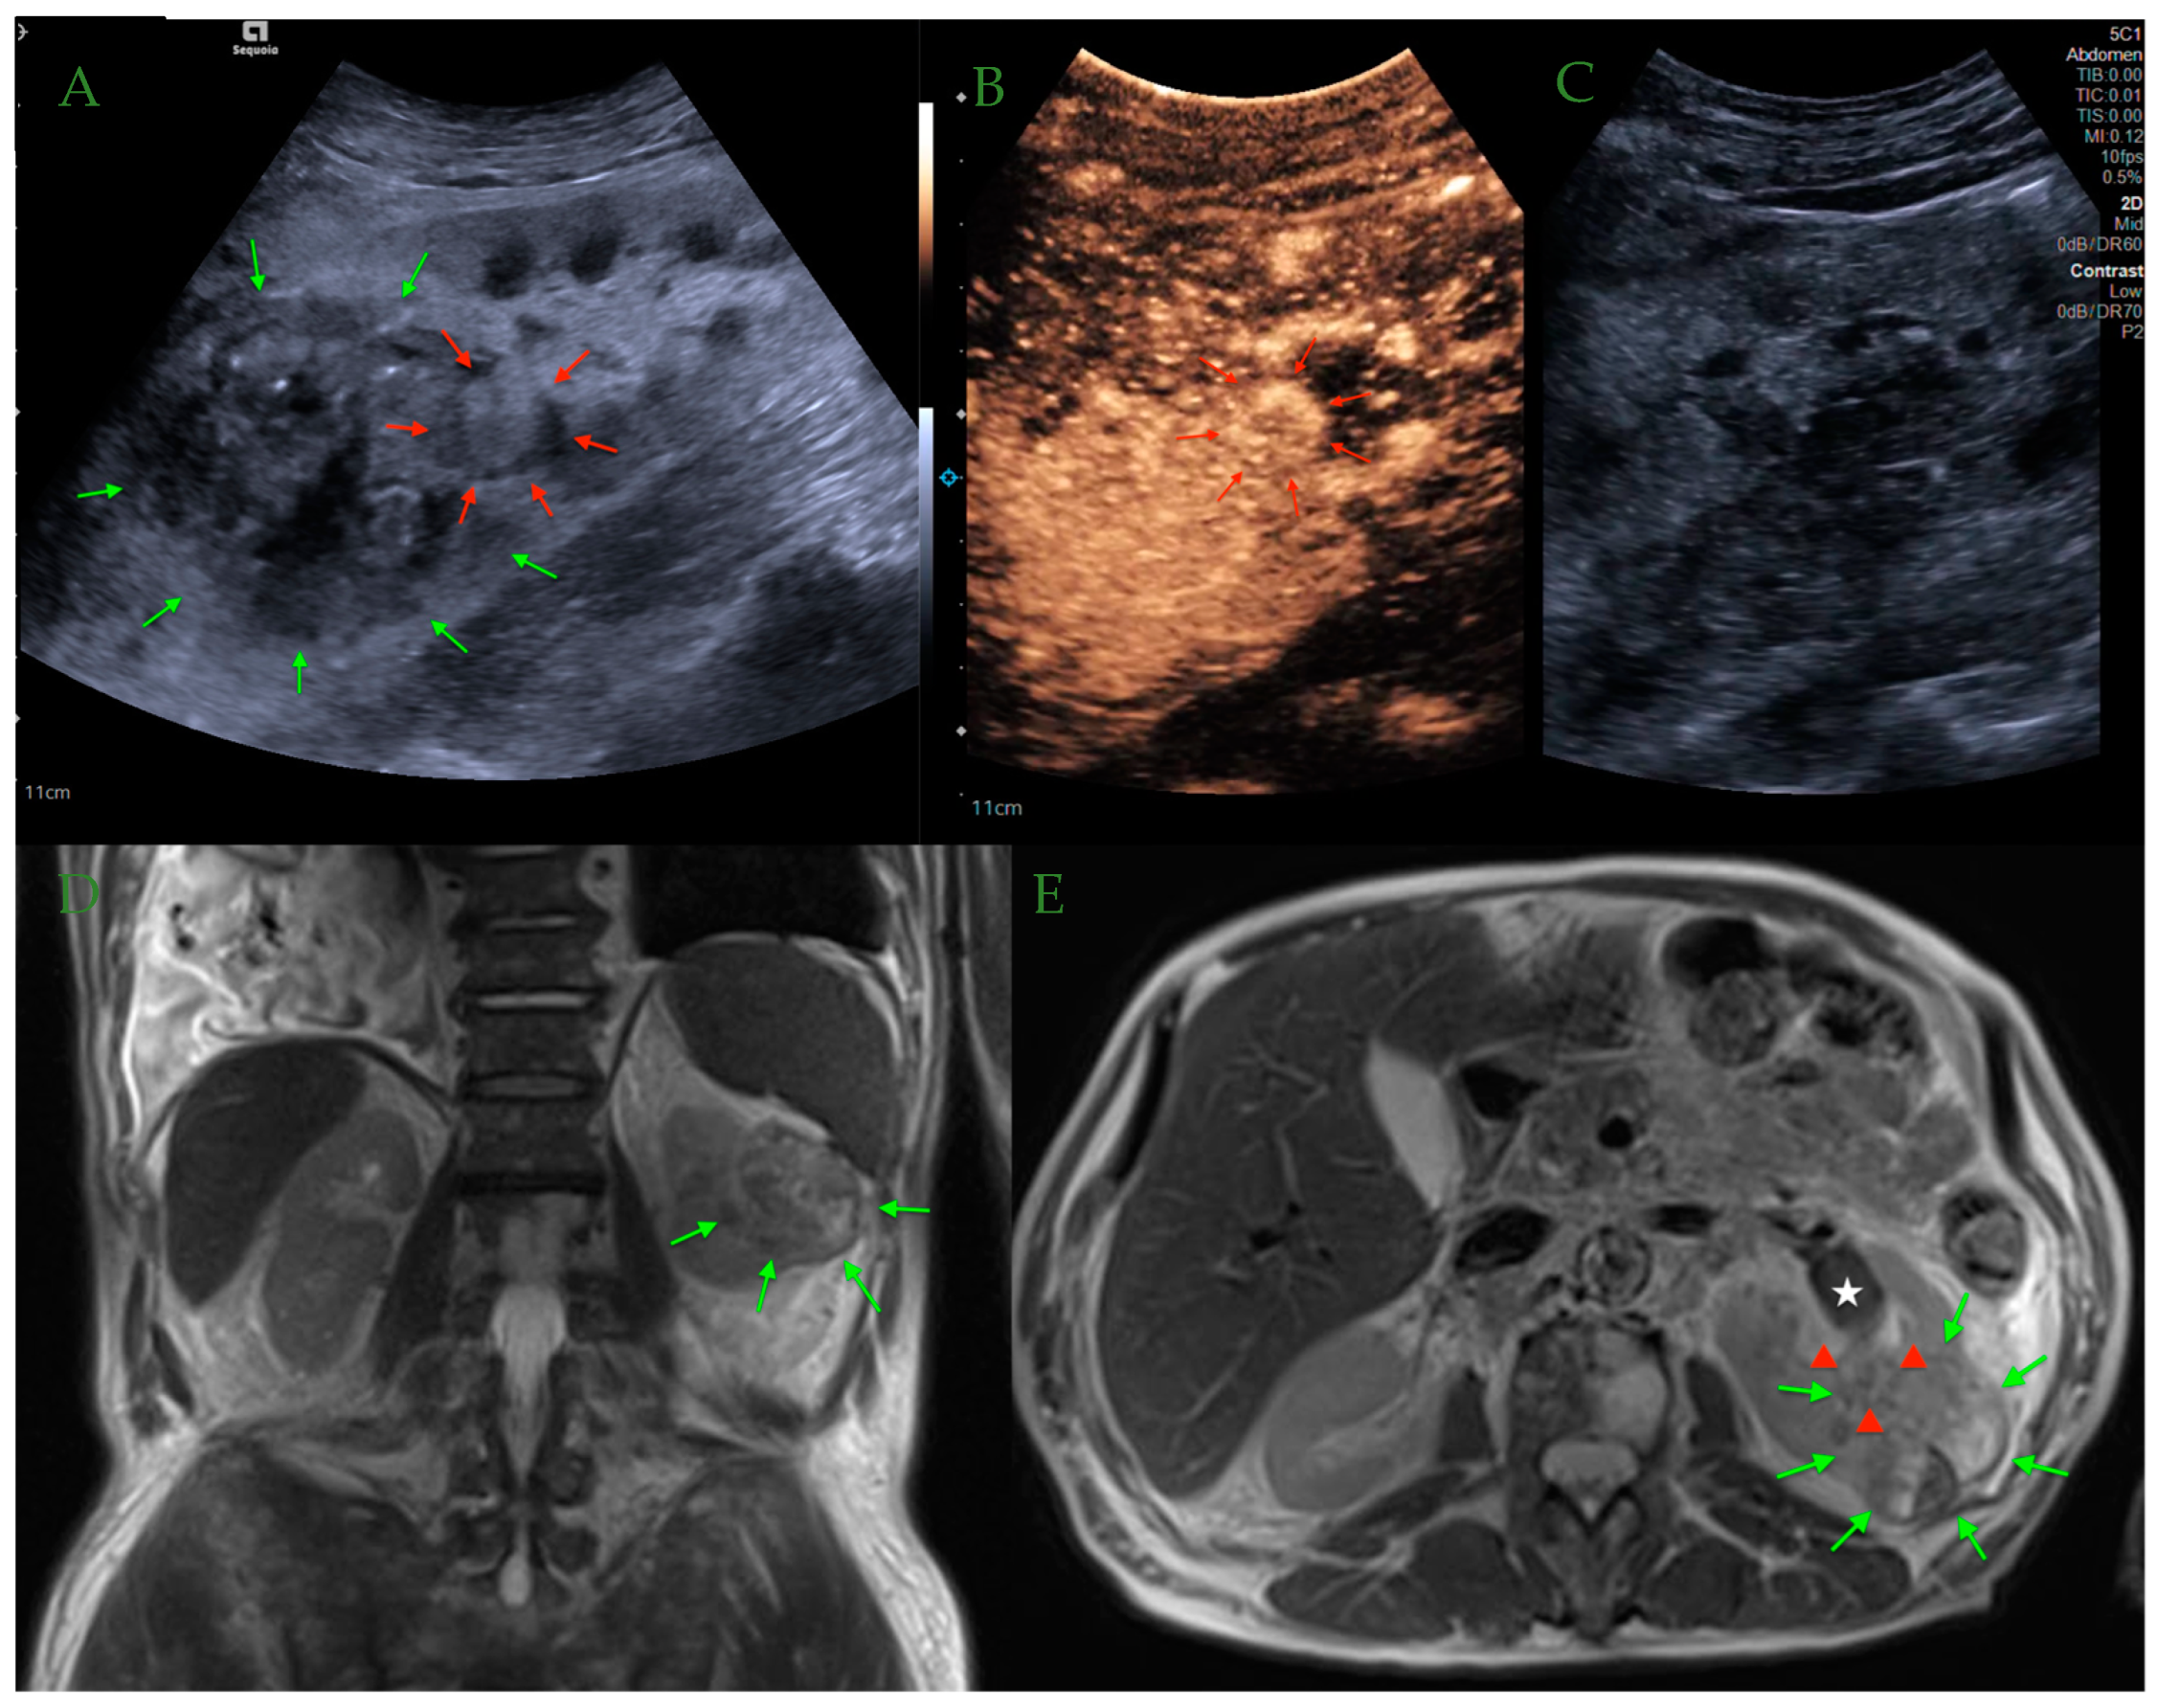

6. Differentiation between Renal Tumors and Pseudotumors in CEUS